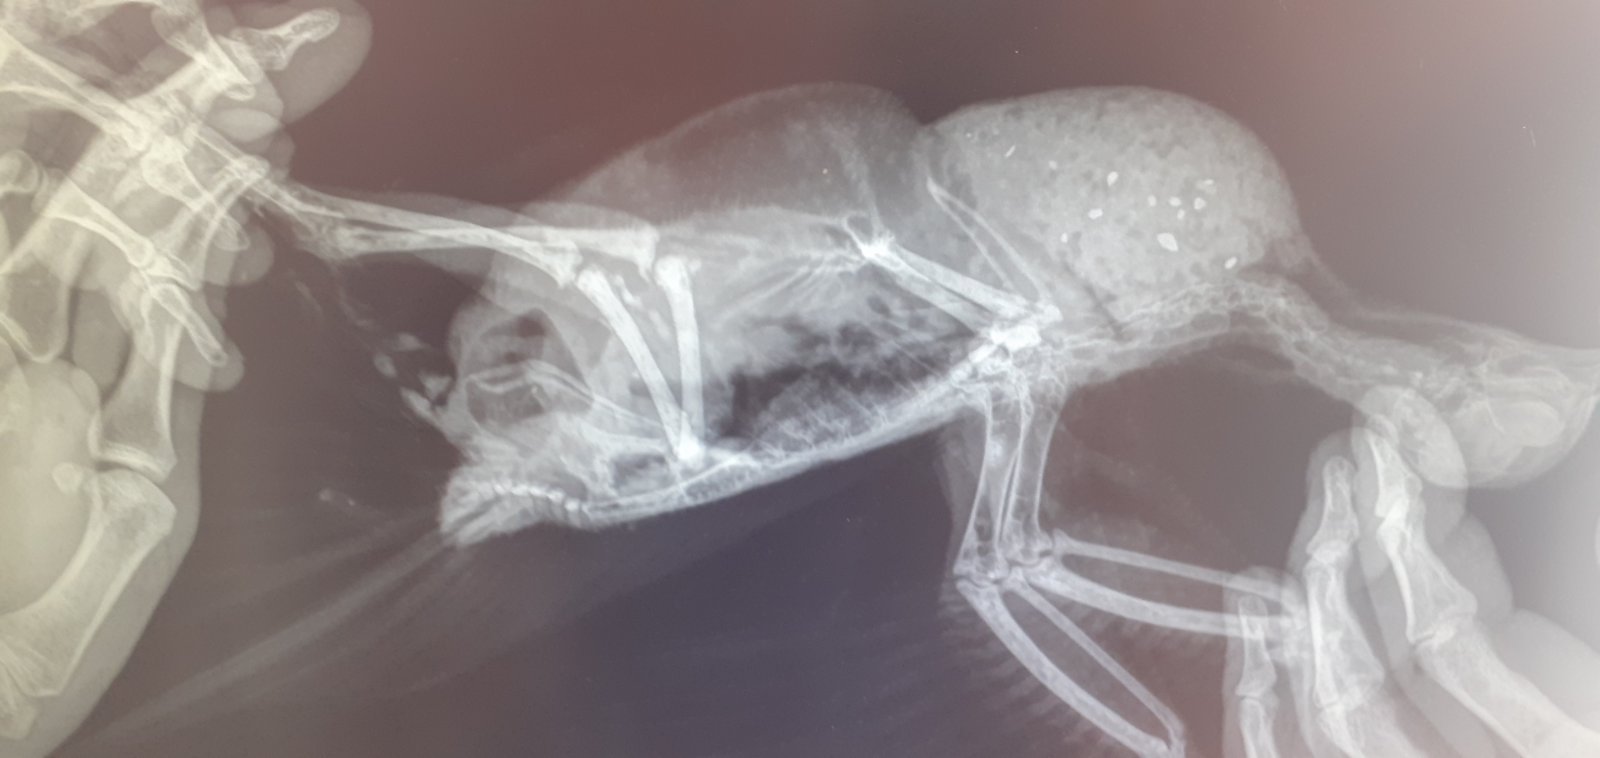

Сделали рентген........ Врач посмотрел, сказал на рентгене яйца нет, но при пальпации яйцо есть но далеко. Остается ждать пока оно не опустится в клоаку. Газового наркоза у нас нет, а если обычный, она не перенесет.

Сейчас кормить кашей, и каждые 2 часа давать раствор  рингера по 2мл. Кальций не давать так как он есть в рингере.

2 раза в день давать ветом на кончике ножа. Давать панкреатин.

20250614_152237.jpg

На счет того, почему птица вытягивает шею буд-то хочет срыгнуть, сказал это интоксикация

только одна проекция?